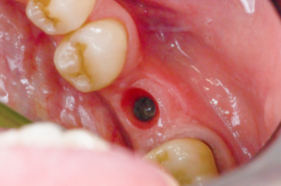

Zubní implantát se zavádí chirurgicky v lokálním znecitlivění.

Došlo-li ke ztrátě kosti, je nutné ji doplnit syntetickým kostním granulátem, vlastním kostním štěpem nebo kost „roztáhnout“.